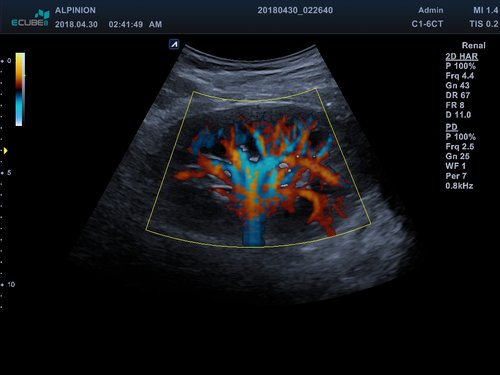

• Powerdoppler: sensitive, farbige Darstellung des Blutflusses unabhängig von Geschwindigkeit und Richtung

• DPDI: Technologie, die Sensitivität des Powerdopplers mit der Flussrichtungsinformation des konventionellen Farbdopplers kombiniert

• C1-6CT (1-6 MHz) für Ultraschalluntersuchungen in Bereichen Abdomen, Geburtshilfe, Gynäkologie, fetales Echo